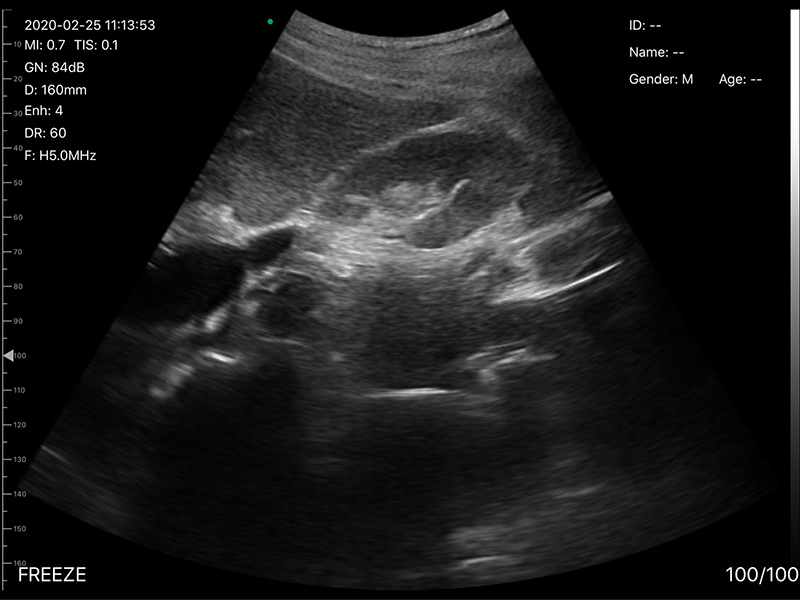

• 探头频率:3.2/5.0MHz

• 扫描深度:90/160/220/305mm,可调

• 图像调节:增益、焦点、反相脉冲谐波、降噪